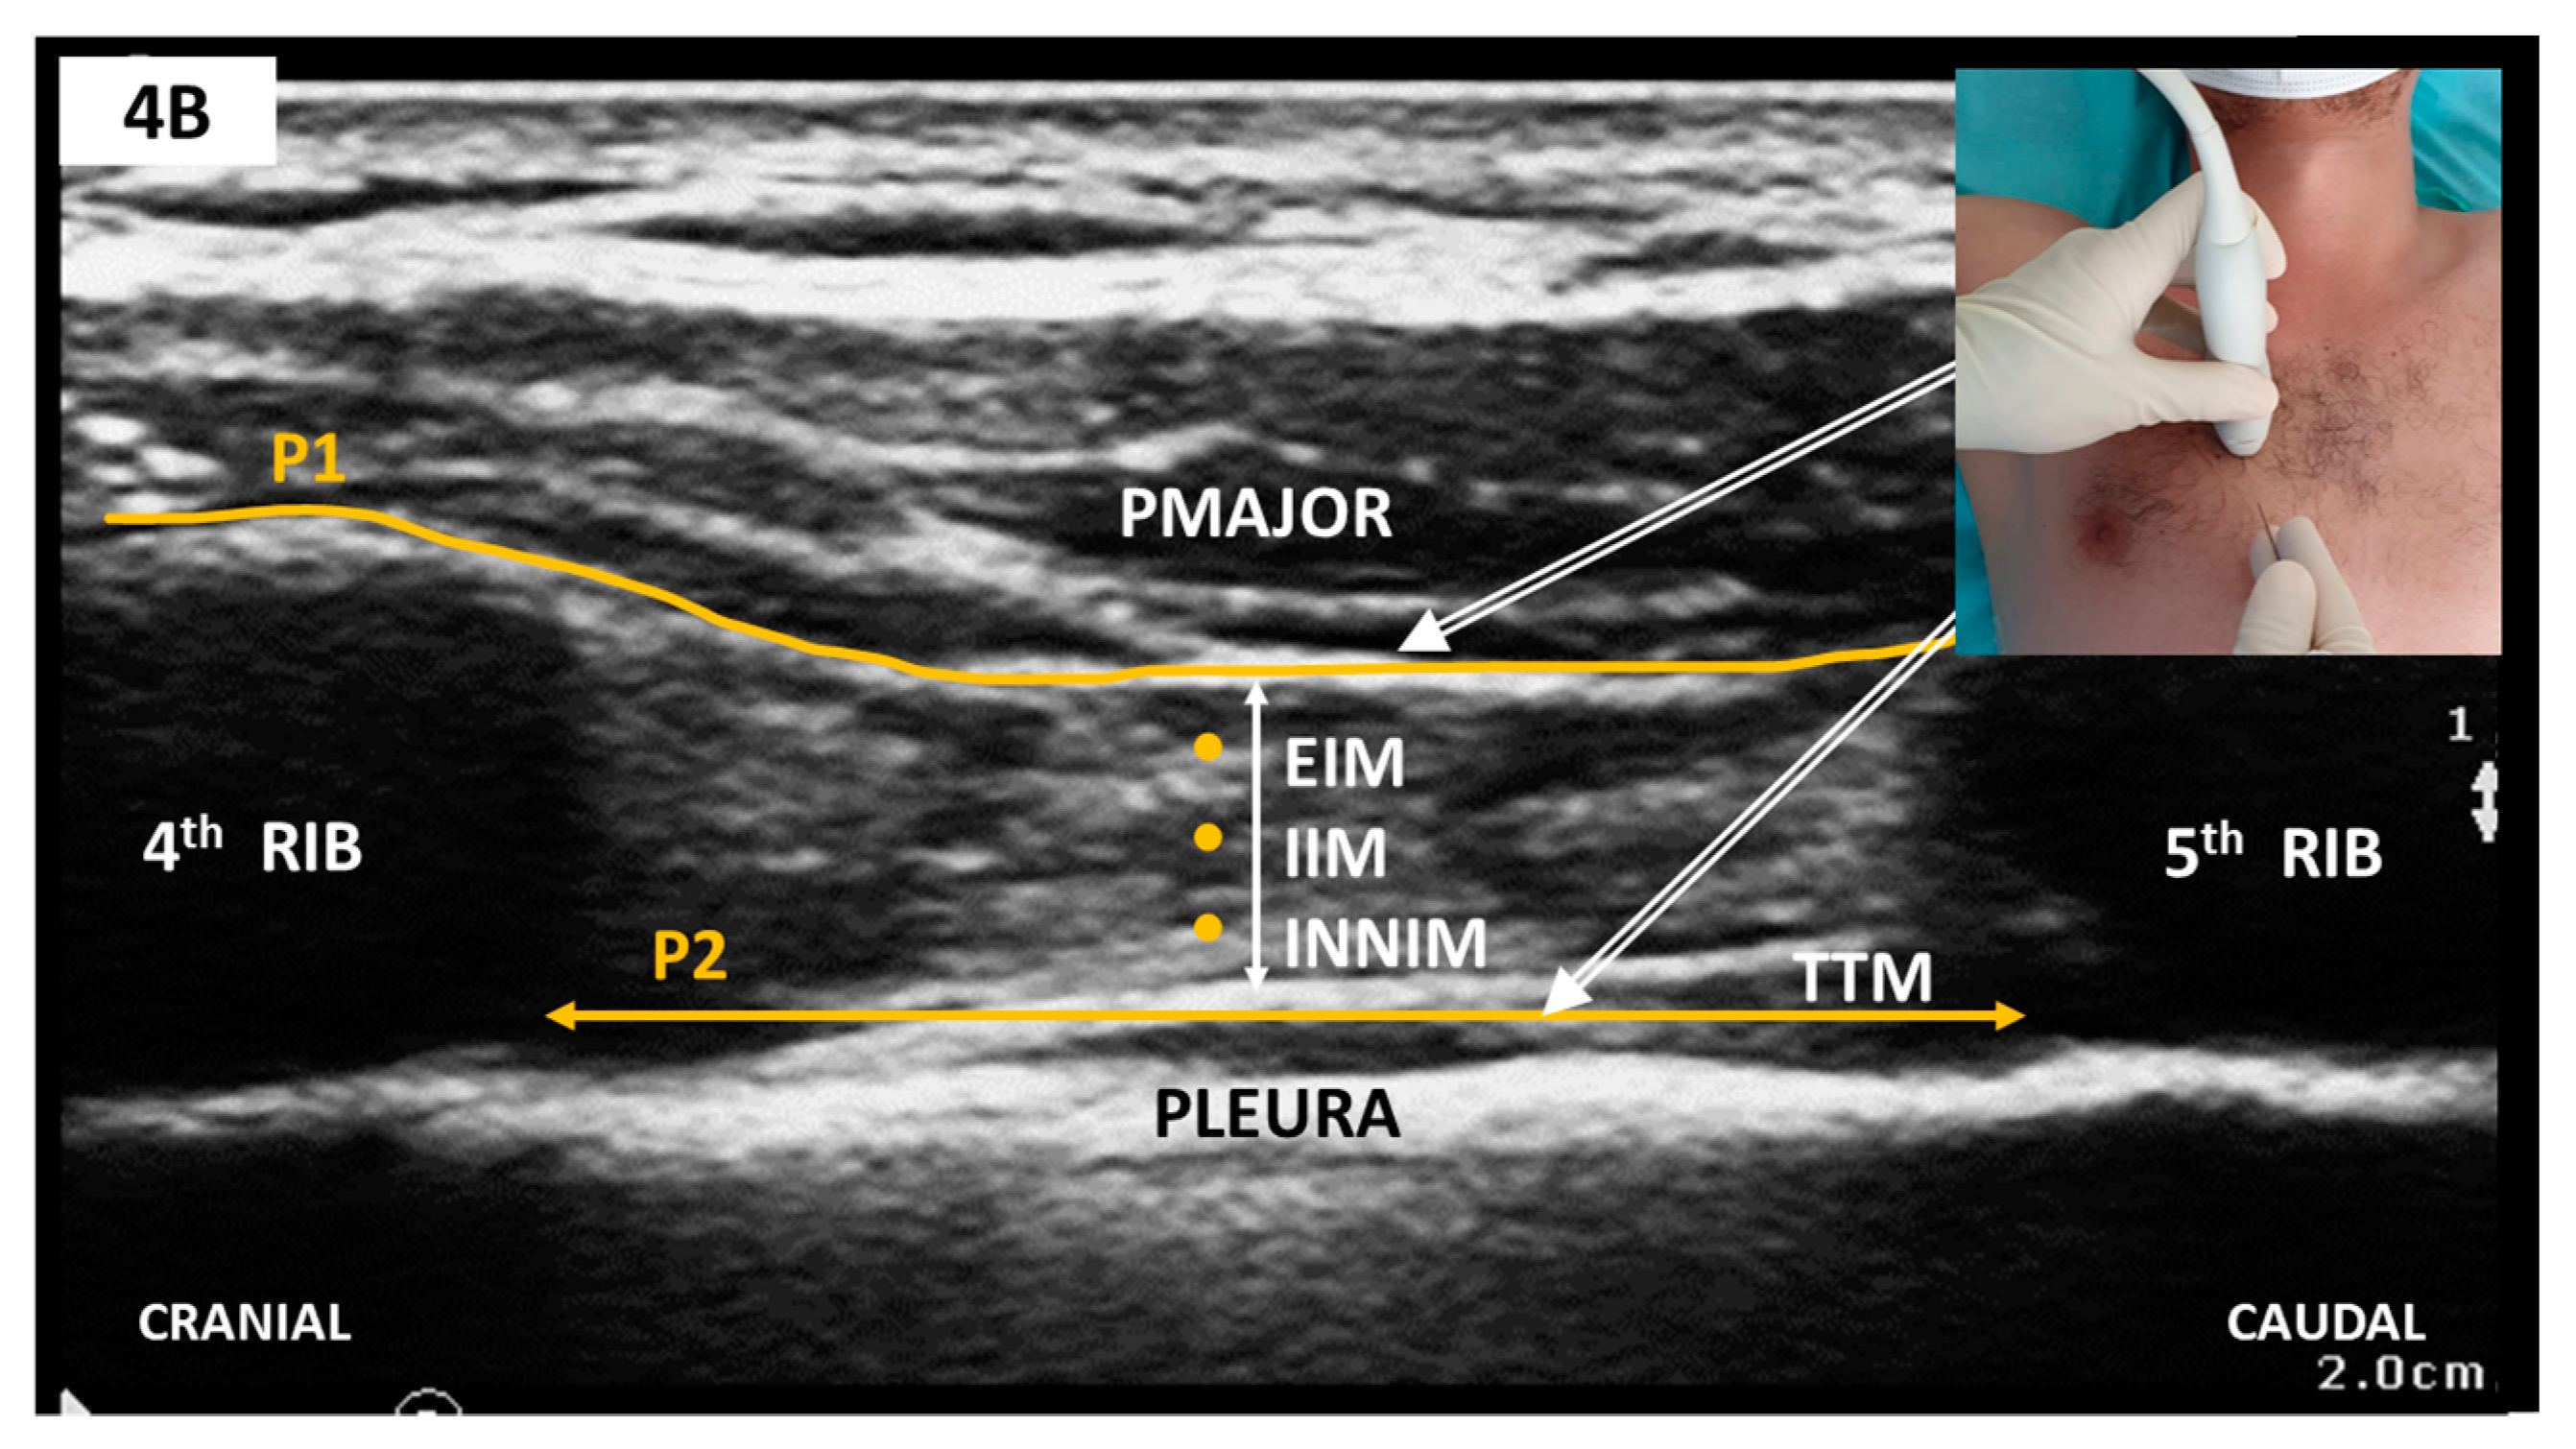

Sonoanatomy and Block Technique (Figure 4)